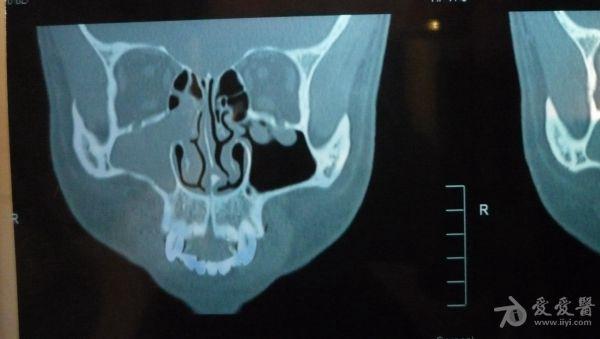

CT结果是右侧上颌窦及部分筛窦窦腔内见稍高密度影填充,CT值约21U,窦壁骨质未见破坏征象;鼻腔后部亦见少量稍高密度影填充;左侧上颌窦、筛窦及蝶窦、额窦未见明显异常。CT图片见附件。医生说我的右边鼻窦都被软组织堵死了,必须要做手术清楚后再做病理分析看是良性还是恶性。

想请问下医生:CT图片上右边的上颌窦内的稍高密度影,是软组织还是液体的几率大些呢